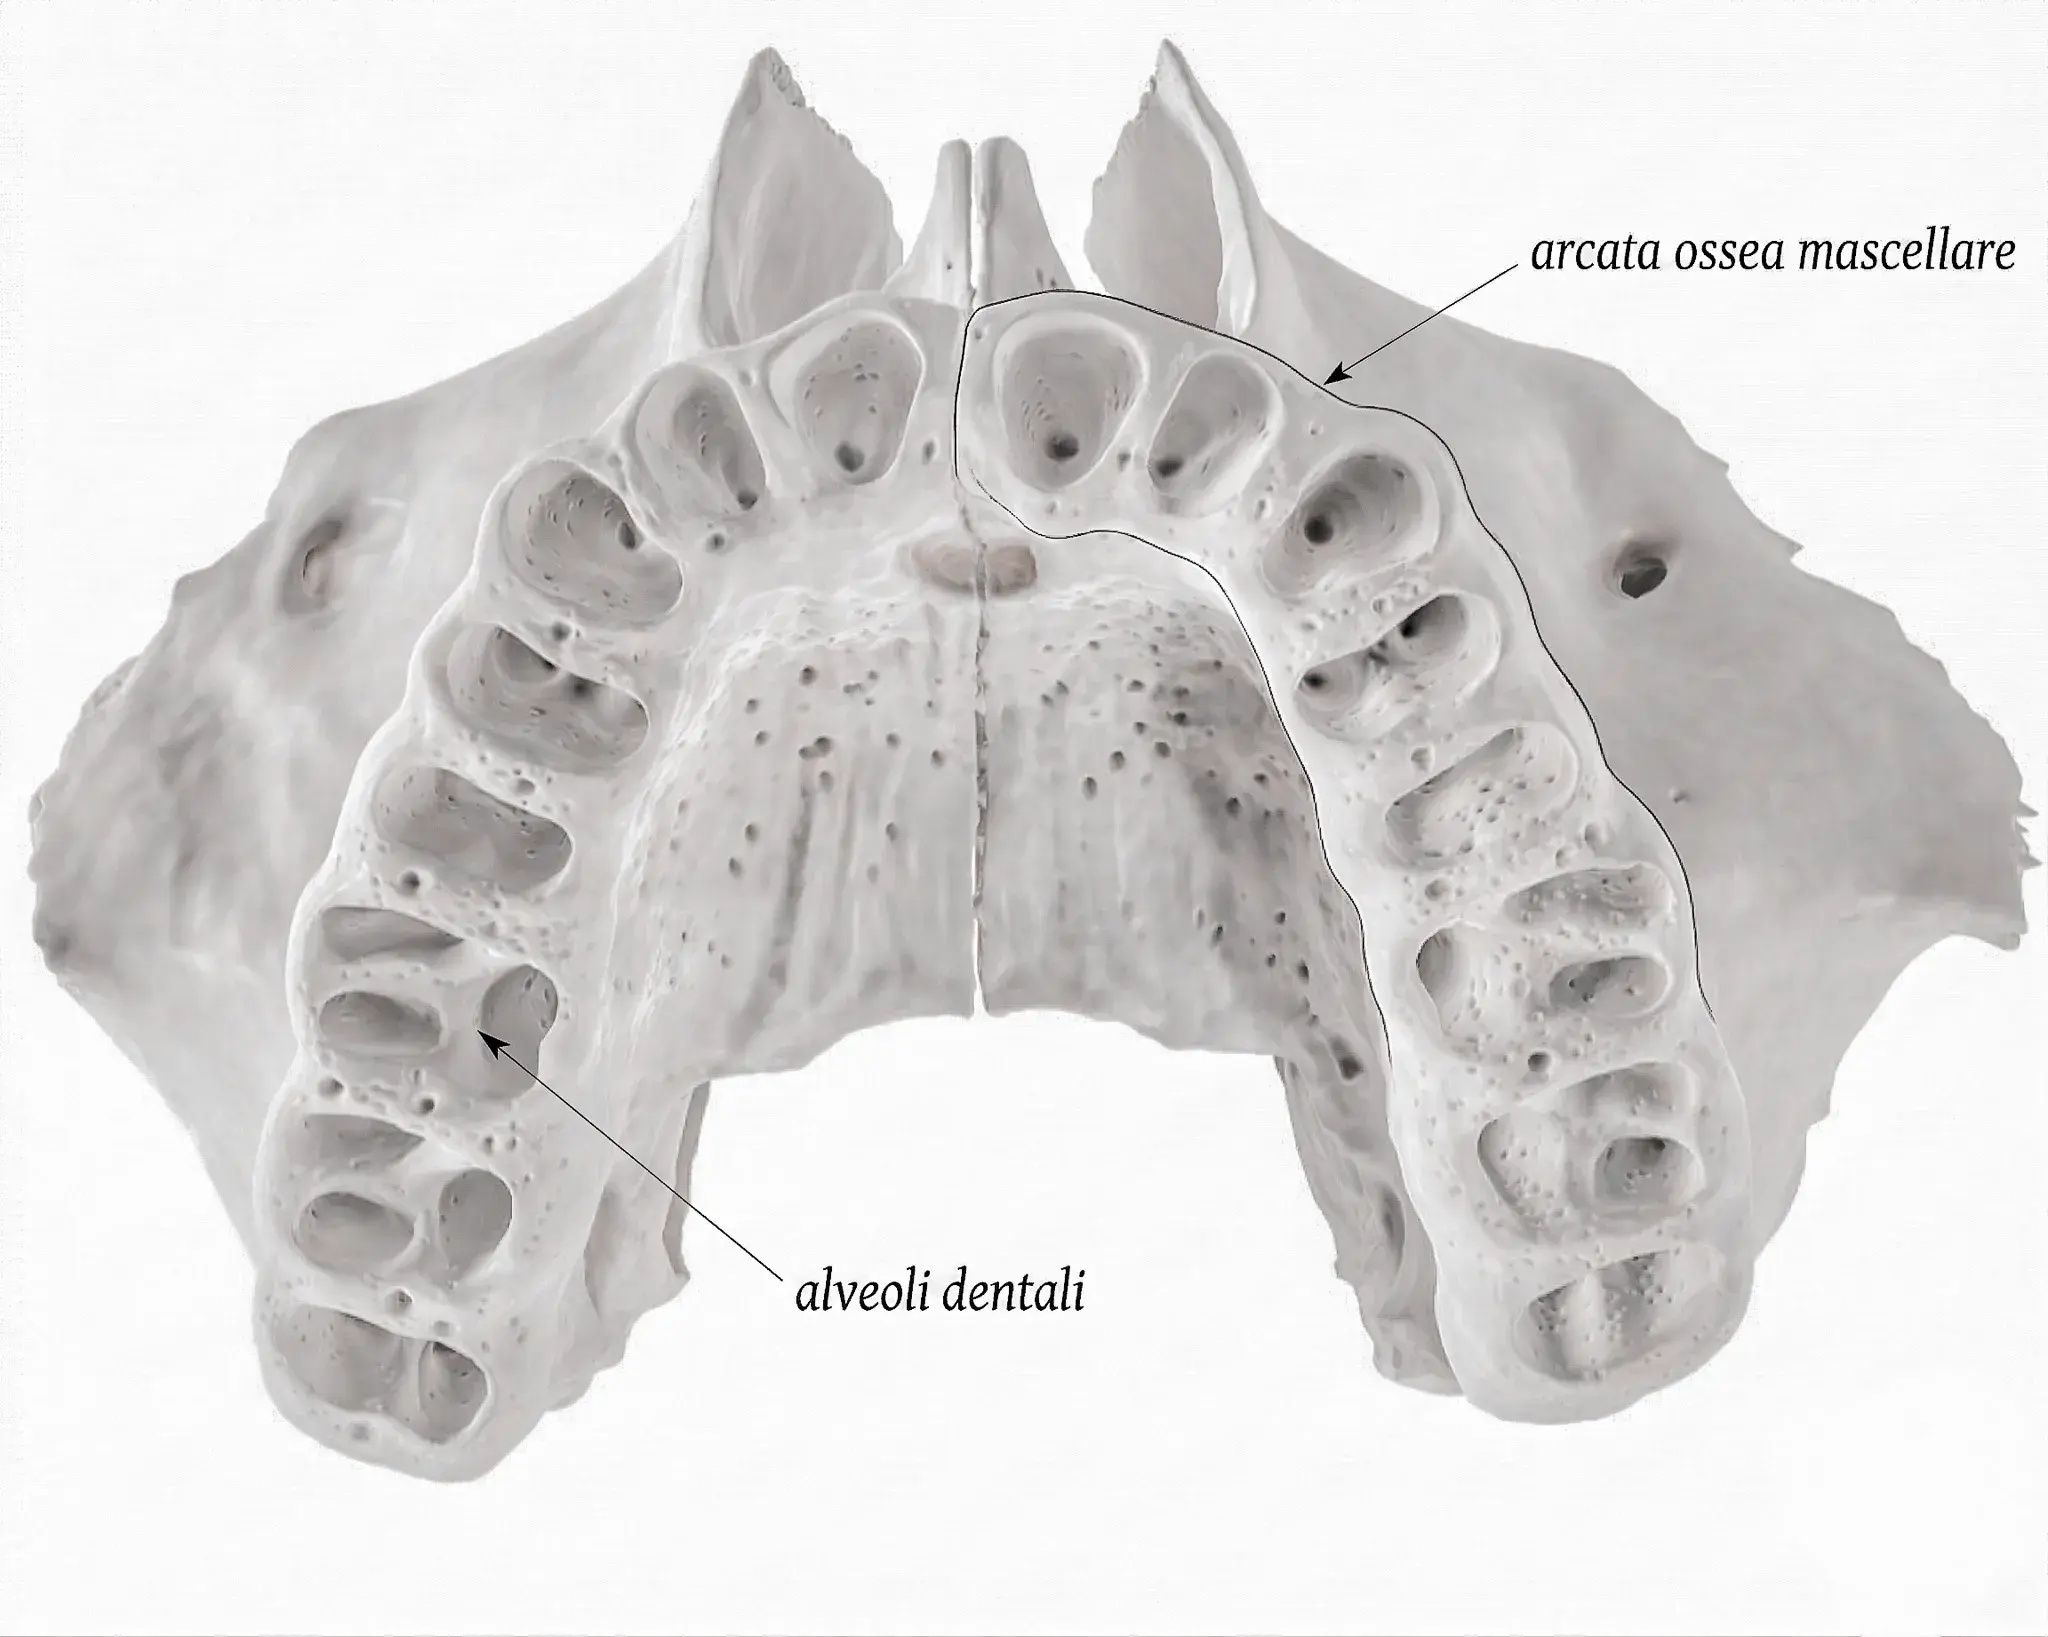

Le ossa con gli alveoli sono mascella e mandibola. Guida all'osso alveolare: anatomia, bundle bone, riassorbimento e preservazione.

Osso alveolare e cresta alveolare: anatomia, bundle bone, riassorbimento post-estrattivo e preservazione. Tutto quello che serve sapere prima di un impianto.

Dopo un'estrazione l'osso si riassorbe perché perde lo stimolo del legamento parodontale. Preservazione alveolare e tempistiche giuste per l'impianto.